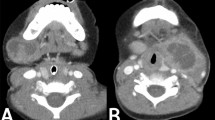

Although enlarged lymph nodes in children are predominantly non-neoplastic, they often cause concern and prompt parental consultation with physicians [7, 8]. Abnormal lymph node enlargement can also be observed, such as lymphadenopathy due to tuberculosis infection [10], inflammation, or lymph node enlargement from malignancies in children, although the latter is rare [6,7,8]. Despite the low incidence of malignancy, a timely and accurate diagnosis is crucial for prompt treatment. The management of pediatric patients with enlarged lymph nodes typically involves obtaining medical history, physical examination, additional blood tests, chest X-rays, or ultrasound examinations to identify the cause of lymph node enlargement or to assess the likelihood of malignancy [5, 11, 12]. Patients with enlarged lymph nodes who have received antibiotic therapy without improvement for more than 4 to 6 weeks [11] or exhibit suspicious symptoms of malignancy such as prolonged fever, weight loss, or lymph nodes larger than 2 cm [3, 5] often undergo further diagnostic evaluation through lymph node biopsy, which is considered the gold standard. Fine-needle aspiration biopsy is generally not preferred in children because of the small size of the obtained tissue [2], which may lead to inaccurate histopathological interpretation [5]. Therefore, surgical excisional biopsy of enlarged lymph nodes in children often requires general anesthesia to obtain lymph node tissue for examination, which may entail risks of complications from anesthesia or surgery [12, 13].

Accurate prediction of the abnormality of enlarged lymph nodes in children based on precise medical history and physical examination can guide treatment decisions, appropriate selection of biopsy sites, reduction of the risk of unnecessary anesthesia and surgery [14], and minimization of surgical complications such as wound pain, infection, or wound dehiscence [12]. Moreover, it alleviates parental anxiety regarding lymph node conditions without the need for confirmatory biopsy and reduces unnecessary healthcare costs. Thus, this study aimed to develop a clinical prediction model to aid in diagnosing histopathological results in pediatric patients with enlarged lymph nodes, providing guidance for treatment decisions and referrals for further evaluation.